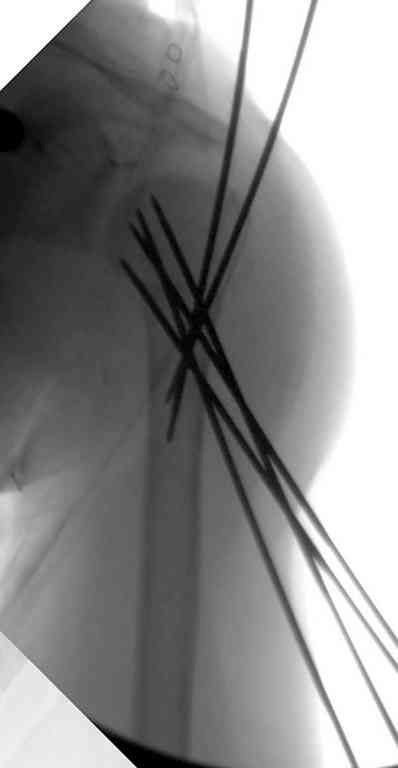

Сделали напряженными спицами по методике А.Ф.Лазарева со товарищи Репозиция сделана спицевым дистрактором, проксимальная спица была проведена в полскости деформации перпендикулярно оси наклонившейся головки. Получилось все довольно легко. Спицы малость покороче можно было сделать, ну да удалять потом легче будет.

Картинка в приложении.

Очень даже неплохо получилось. Молодцы! Лучше чем на 3D "репозиции".

Все заняло 1 час. Собственно введение фиксаторов - минут 20.

Оставили в косынке, сразу разрешены маятникообразные движения в плечевом суставе. Дальше по ходу расскажу.